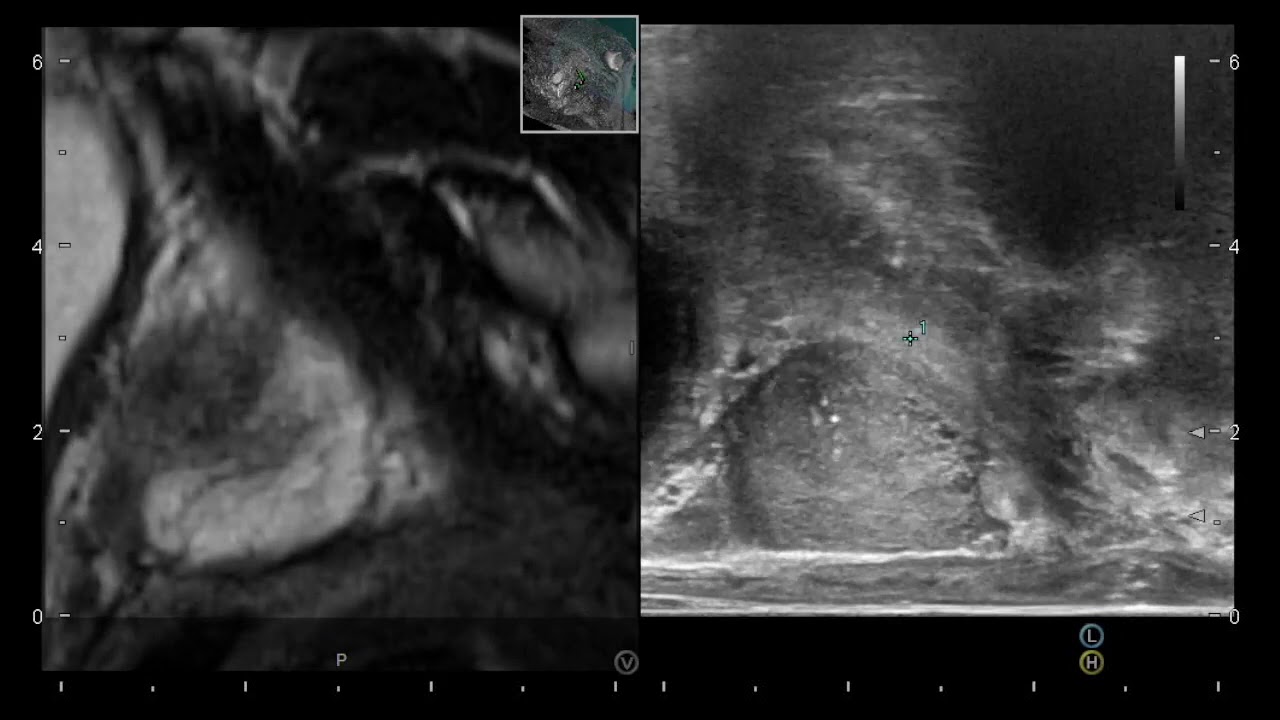

Mi nombre es Miguel Ángel Rodríguez Cabello. Soy médico licenciado por la Universidad de Alcalá y especialista en Urología formado en el Hospital Universitario Ramón y Cajal. Terminé mi formación como especialista en Urología en el año 2015 de la mano de grandes profesionales y maestros, y trato de transmitir todos mi conocimientos y habilidades para el beneficio de mis pacientes. También he completado mi etapa universitaria con el Doctorado, que defendí en la Universidad Autónoma de Madrid en junio de 2023 con resultado Cum Laude. He recibido formación en cirugía robótica (INTUITIVE - DaVinci Xi y SP) en Saint Augustin Clinic de (Burdeos) y estoy acreditado para su utilización por la agencia IRCAD (Strasbourg, France) desde 2017. Tengo amplia experiencia en el manejo de la hiperplasia de próstata con técnicas como la enucleación y vaporización con láser y con la moderna técnica robótica denominada hidroablación - AQUABEAM -, Por último, mi campo de trabajo e investigación más puntera es el diagnóstico y tratamiento del cáncer de próstata (biopsia fusión, terapia focal, prostatectomía radical...), temática que abarca gran parte de mi actividad profesional.

Diagnóstico y tratamiento en cáncer de próstata (biopsia de próstata por fusión, terapia focal, prostatectomía radical, nuevas tecnologías...).

Biopsia de próstata por fusión. Cirugía robótica (DaVinci, AQUABEAM). Cirugía de la hiperplasia de próstata con láser, REZÜM y Aquabeam. Terapia focal en cáncer de próstata (crioterapia, HIFU). Vasectomía sin bisturí. Circuncisión sin bisturí (CIRCURER). Segundas opiniones médicas. Ensayos clínicos en infecciones del tracto urinario.